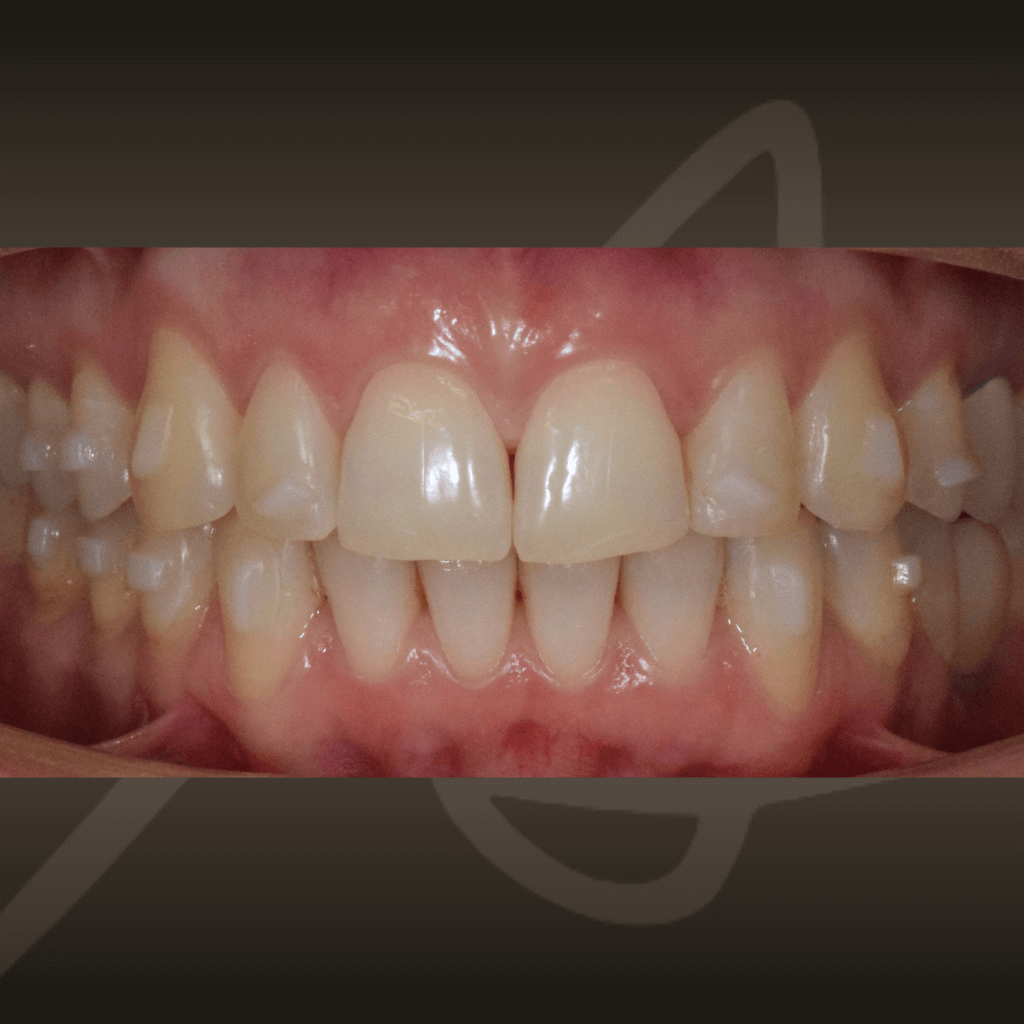

Ортодонтията не е само въпрос на подредба. Правилното лечение подобрява захапката, речта и създава стабилна основа за дългосрочно дентално здраве. Независимо от възрастта, ортодонтското лечение може да допринесе за по-добър функционален баланс и по-лесна поддръжка на зъбите във времето.